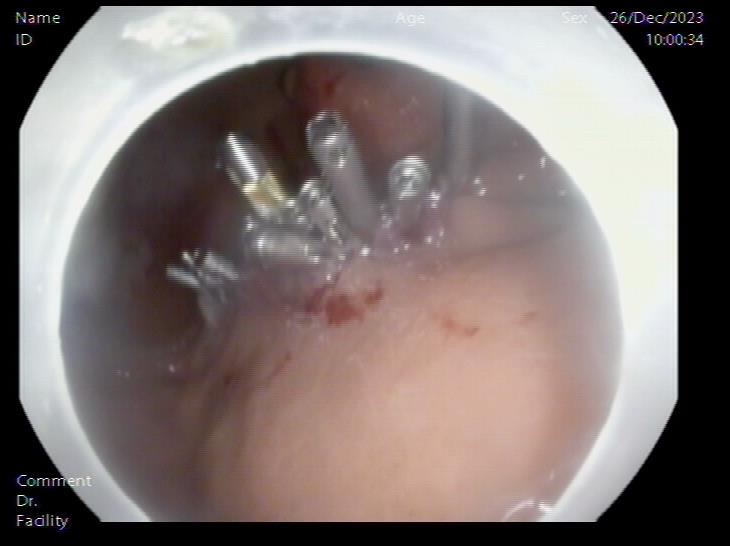

囊肿切开引流,囊壁塌陷 内镜下胃壁全层缝合

患者,66岁,女性,平素身体健康,以“发现胃肿物2年余”主诉入院,既往于外院行电子胃镜检查发现胃底隆起,直径约1.5-2.0cm,超声内镜检查考虑黏膜下来源间质瘤可能,不除外壁外病变压迫。外院CT提示胃底浆膜下囊性病变可能。患者及家属诊治心切,辗转数家医院后为求内镜下治疗遂来二附院。入院后在消化内科再次超声内镜检查,提示胃壁增生病变可能,增强CT提示胃底胃壁增厚,结合内镜检查。患者及家属强烈要求内镜下探查及病变切除术。术前在王进海主任的指导组织下,进行了专业组内及多学科讨论,与患者及家属充分沟通后,决定行内镜下切开探查及病变治疗术,必要时可行内镜-腹腔镜联合手术(LECS)。邹百仓教授带领内镜下肿瘤诊治及超级微创手术团队施行手术,术中逐层切开胃壁黏膜层及黏膜下层,暴露固有肌层,未发现胃壁病变,遂切开胃壁全层,局部腹腔探查,切口附近腹腔内似韧带组织上发现半球形隆起,表面透亮光滑,大小约1.5X1.5cm,术中请外科李军辉及袁庆攻教授会诊后确诊为囊性病变,讨论后建议可以观察或内镜切开引流,与患者家属沟通后家属强烈要求切开引流,遂用内镜切开刀切开囊肿,引流少量清亮囊液,囊肿塌瘪,观察囊肿切口及局部无出血,切除局部部分胃壁组织送检,内镜下严密关闭切口,留置胃管后,返回病房,常规对症治疗1周,患者无并发症发生,正常出院。